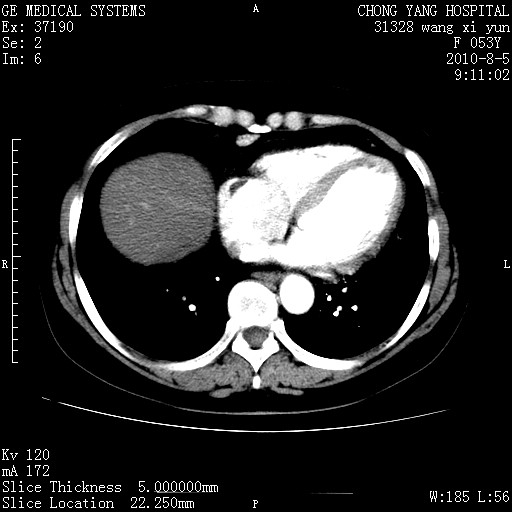

1)考虑肝左叶胆管细胞癌。2)脂肪肝。